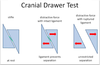

In a Partial Tear of the Cranial Cruciate Ligament, there will be a Positive Cranial Drawer or Tibial Thrust ONLY when the Joint is in Partial ______

Flexion

*When the Stifle is in Extension, it will Appear Stable